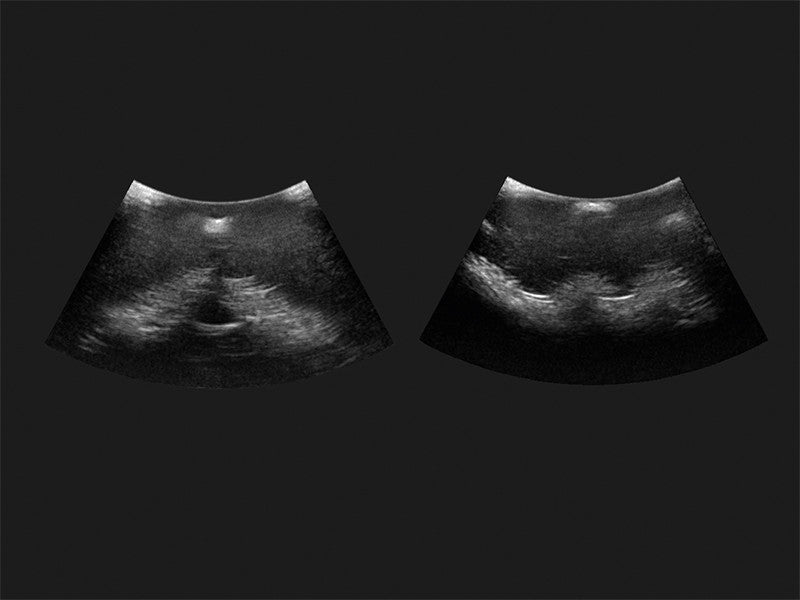

Our range of epidural injection trainers includes detailed anatomical models that replicate the lumbar and thoracic spine, providing a hands-on learning experience for anaesthetists, medical students, and pain management specialists. These advanced simulators allow users to practise needle placement, identify key anatomical landmarks, and develop proficiency in administering epidural and spinal anaesthesia with confidence. Ideal for medical schools, hospitals, and professional training programmes, these epidural trainers support skill development in regional anaesthesia, labour pain management, and spinal procedures. With lifelike materials that simulate real patient responses, our models offer a realistic and immersive training experience.